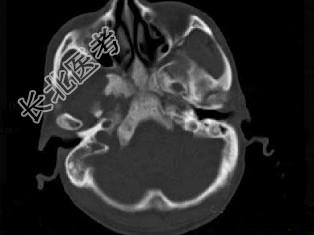

- 单项选择题男性,56岁, 鼻咽癌放疗后复查,CT扫描如图所示, 请选择正确的答案 ( )

D、放疗后骨炎